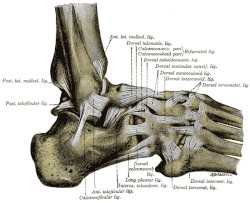

Anatomie

Das obere Sprunggelenk des Menschen (es gibt auch ein unteres Sprunggelenk [USG] unterhalb des Sprungbeins) besteht aus dem Wadenbein (Fibula), dem Schienbein (Tibia) und dem Sprungbein (Talus). Straffe Bänder halten die mit Knorpeln überzogenen Gelenkenden dieser Knochen zu einem Gelenk zusammen: Das vordere und das kräftigere hintere Syndesmosenband verbinden Waden- und Schienbein zur Sprunggelenkgabel; der Schaft des Wadenbeins und des Schienbeins am Unterschenkel darüber sind durch das funktionell gleichwertige flächige Zwischenknochenband (Membrana interossea) verbunden. Das in die Sprunggelenkgabel eingepasste Sprungbein wird durch die Außen- oder Seitenbänder (Ligamentum fibulotalare anterius, Ligamentum fibulocalcaneare und Ligamentum fibulotalare posterius) und das etwa dreieckige Innenband (Ligamentum deltoideum) beweglich, aber stabil gehalten. Die aktive Stabilisierung des oberen Sprunggelenkes erfolgt über die peronealen (fibularen) und tibialen Sehnen parallel zum Bandapparat und über die gelenkübergreifenden Streck- und Beugesehnen mit der Achillessehne. Die Lastübertragung des Fußes auf den Unterschenkel erfolgt ausschließlich über das Sprungbein und die untere Gelenkfläche des Schienbeins. Die Knöchel dienen dabei der seitlichen Führung des Gelenks. Der Innenknöchel ist integraler Bestandteil des breiten, unteren Schienbeinendes, während der Außenknöchel die gelenkseitig überknorpelte Spitze des Wadenbeins darstellt.